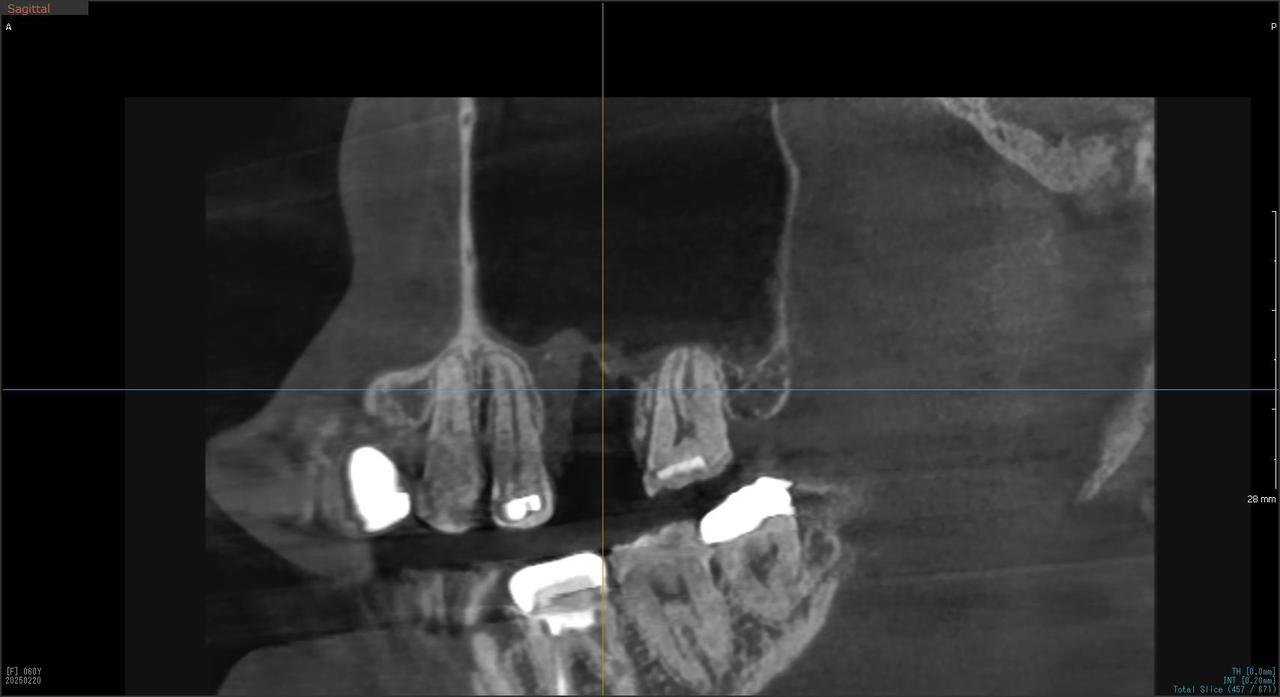

5.右上6番の歯根が破折したに大きな骨欠損を生じたケースに対して、通常なら、大幅な増骨手術(GBRとサイナスリフト)が必要で、最低1年は、かかるケースを、骨補填材なしで、インプラント埋入後、2.5か月で治療を終えたケース

症状としては、左上6番の歯根が歯根が破折したために、炎症が起き、上顎洞底までの及ぶ大きな骨欠損がおきていた、

治療法としては、動揺がひどくなってきて、炎症の症状もあったため、抜歯を希望。抜歯後にインプラント治療を希望したために、CTを撮影したところ、かなりの骨欠損が生じていた。インプラントは不可能か大幅な増骨手術が必要なるようなケースであったが、ご自分の骨が少し残っていた部分にエクストラワイドインプラントで固定をとることと、グラフトレスサイナスリフトを併用する計画を立て、インプラント埋入術を施行。2か月後、インプラントがデータ測定上安定したために、光学印象で印象を行い、2か月半後に上部としてジルコニアクラウンを装着して治療を終えています。

治療結果として、大幅な骨欠損があったが、2か月半という短時間で治療を終えることができた。通常のサイナスリフト等の大幅な増骨手術を行った場合、患者様に、肉体的、金銭的、時間的な負担をかけることになったが、グラフトレスサイナスリフトとエクストラワイドインプラントを使用することにより、そのことを避けることができた。

治療の期間・回数:治療回数インプラント埋入後6回

治療の価格:363000円(税込)

治療費の内訳:インプラント基本料(フィックスチャー(メガジェンインプラントANYONE) 及び手術費用、投薬費用、レントゲン費用、インプラント上部費用(アバットメントおよびジルコニアクラウンの費用用)330000円(税込み)左上6グラフトレスサイナスリフト費用 33000円(税込)

治療のリスクや副作用:手術後に、痛みや腫れ、出血、合併症などを引き起こす可能性があります。噛む感覚がご自身の歯と異なる場合があります。見た目がご自身の歯と異なる場合があります。手術後にメインテナンスを継続しないと、インプラントが抜け落ちる可能性があります。